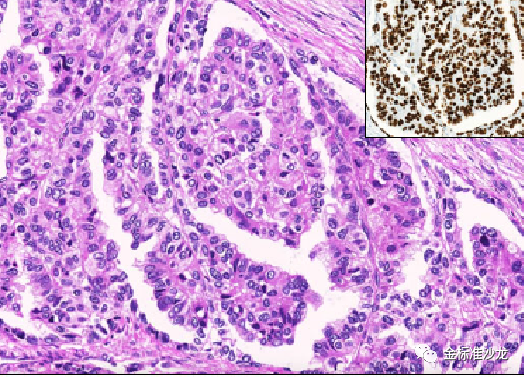

3.反极性乳头状肾肿瘤

最近描述的另一个新兴实体,并具有特征性的组织学形态典型形态(图6)。肿瘤由具有透明或水肿的轴心的乳头结构组成,被覆丰富胞浆嗜酸性细胞,细胞核小、低级别且位于细胞顶端(反极性)。目前报告的病例临床预后良好,无复发,转移或死亡。免疫组化方面,特征性核表达GATA3,以及L1CAM。分子方面,KRAS突变在大多数肿瘤(约80%)中被发现。该肿瘤在文献中报告的数量增长迅速,过去2-3年报告超过90例。该肿瘤常呈囊性,并可与与其他RCCs同时发现。

图6 肿瘤由宽大乳头构成,具有硬化的轴心;被覆细胞嗜酸,具有小圆形的核及反极性。细胞弥漫GATA3阳性表达